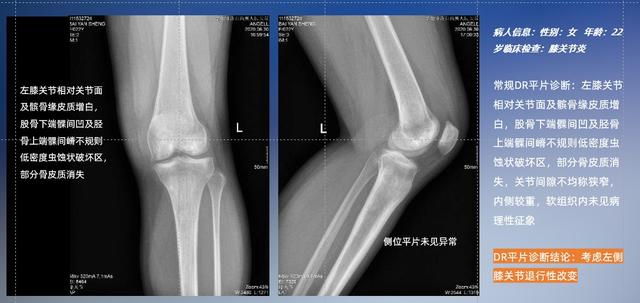

普通平片扫描与WR-3D扫描前后诊断结果对比

以膝关节疾病检查为例,膝关节在解剖学意义上是一种较为复杂的最大关节,由胫骨上端、股骨下端及髌骨组成。在股骨与胫骨的关节面之间存在两块半月板,分别处于内侧、外侧。膝关节的运动主要为伸、屈,在半屈位时可进行小幅度的旋外、旋内运动。随着现代人们体育生活以及肥胖的增加,膝关节疾病出现高发趋势,特别是关节磨损、膝关节炎与骨关节炎等关节退行性改变,长时间的内翻负荷会造成内侧关节软骨、骨性关节面的磨损。目前针对此类疾病的检查主要为平片下的负重位检查、CT检查以及MRI检查,相较于非负重位检查,负重位检查能更加真实反映膝关节结构中胫骨、股骨、髌骨实际对位关系和关节面的形态特征及关节间隙大小,对膝关节骨关节病诊断准确率高。

与此同时,数字化X线摄影技术相较于CTMRI来说,能快速获取真实、直观、满足临床需要的影像。DR的图像具有图像层次丰富、空间分辨力高、影像边缘锐利清晰、密度分辨力高级细微结构表现出色等特点,针对膝关节解剖结构数字化X线摄影技术应用价值很高,尤其是是对骨小梁与骨皮质的显示非常清楚。在负重位状态下,数字化X线三维摄影扫描与重建,能够更好的呈现受检者关节受力改变的状态。必一运动科技创新的WR-3D动态三维数字化X线摄影技术,通过数字化X线摄影完成三维扫描并重建三维影像信息,包括MPR多平面重建、MIP重建以及VR绘制。扫描时间短,剂量相较于CT设备大幅缩减,同时成本更低,在临床诊断以及医疗方案制定中具有极大的价值意义。相较于普通平片下的负重位扫描,负重位动态三维扫描摄影技术能够避免二维状态下的组织结构重叠、密度分辨率不足、组织解剖结构难以分辨等问题,WR-3D支持多角度的动态三维摄影观察,能全面的呈现被检查部位在多个角度下三维影像信息,极大的减少了二维负重位检查的漏诊率。